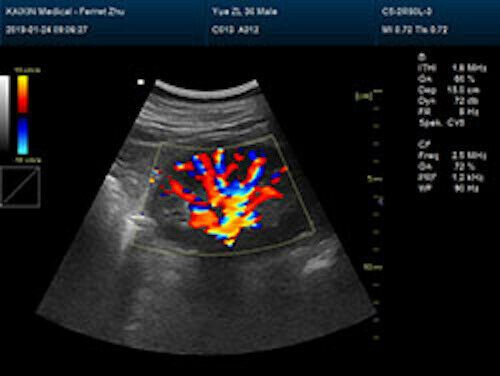

Large Animal Veterinary Color Doppler Ultrasound & Rectal Probe

| Rich clinical application function • B+CF (Dual Images) • B+CF/PDI/DPDI+PW (Triplex) • Convex extended imaging technology • Linear array deflection/Trapezoidal imaging technology • Spatial compound Imaging technology • Panoramic imaging technology (optional) • 3D/4D imaging technology (optional) • Speckle noise removal technology • Pulse inversion tissue harmonic imaging technology (iTHI) |